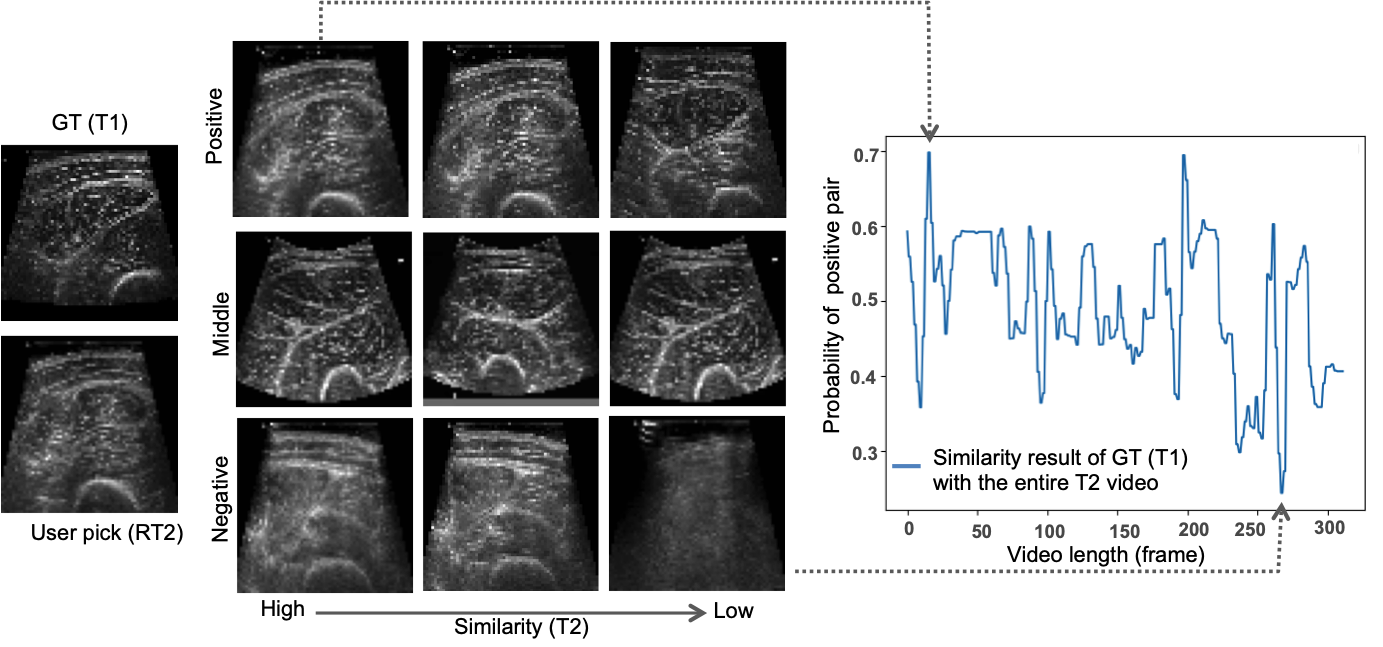

As shown in Table 1, our proposed method achieved superior performance in terms of AUC, precision, recall, and F1-score compared to all other models. The NCC method demonstrated the lowest performance, as it lacked the capability to accurately capture dynamic changes and deformations in US images which can result in significant structural differences. A representative example of a model-retrieved view for one case is presented in Fig. 4. It shows positive,

Refer to caption

Figure 4: Results showing three sample positive, medium and negative predicted pairs by our model when ground truth (GT) from T1subscript𝑇1T_{1} is compared with the T2subscript𝑇2T_{2} video.

negative, and middle (i.e., images with a probability value between the highest and lowest values predicted by our model) pairs of images generated by our model from a patient’s left leg. As reference, on the left we show the user pick (RT2𝑅subscript𝑇2RT_{2}).